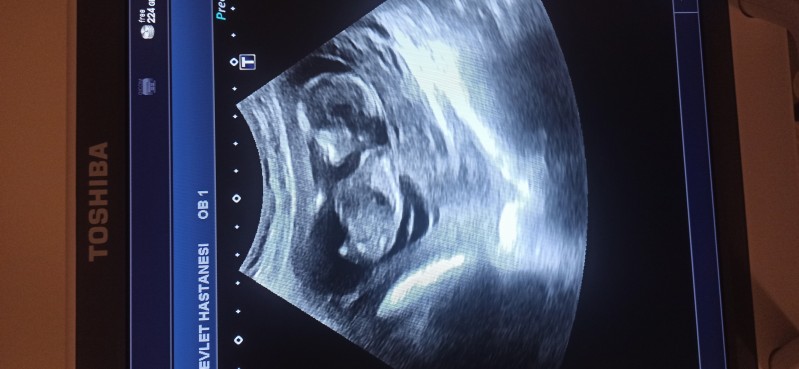

Merhaba arkadaşlar cinsiyet tahmini yapabilecek olan var mı acaba?

Kıza benzettim sağlıkla gelsin inşallah

Erkek gibi sanki

Başı yuvarlak ve küçük, kız gibi.